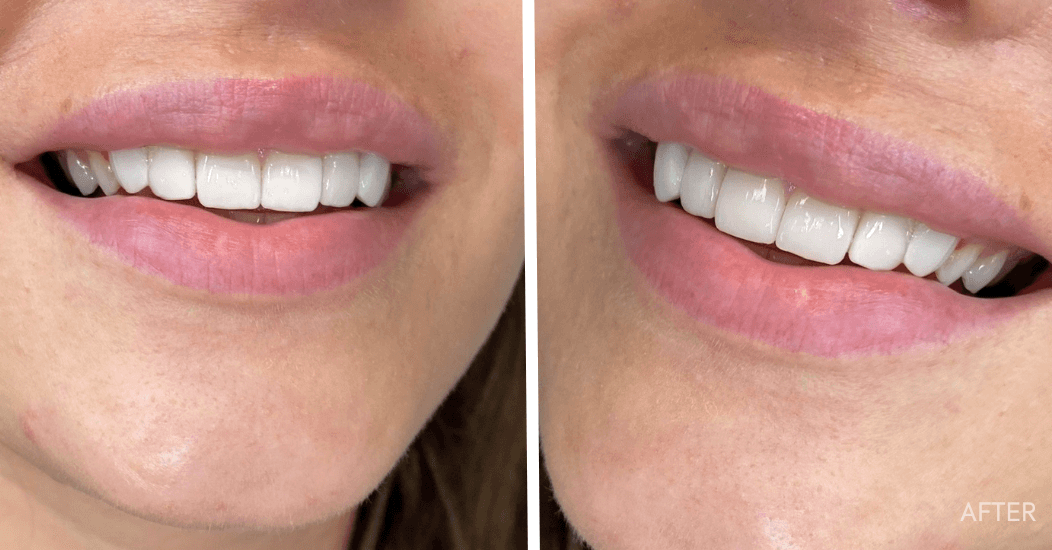

Преди и след

Резултати на нашите пациенти